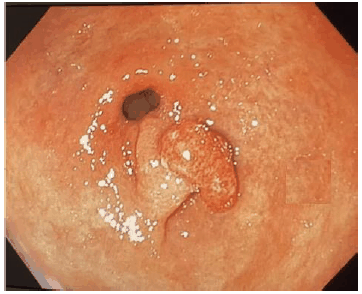

Analise a imagem a seguir.

De acordo com a classificação de Paris, a imagem acima é corretamente classificada como